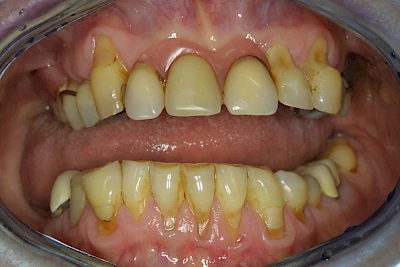

Über die Zeit können verschiedene Prozesse die Zahnhartsubstanzen aufzehren:

- Abnutzung durch Kauen (Abrasion) oder duch durch übermäßiges Knirschen bzw. Pressen (Attrition)

- Säurebedingte Auswaschung (Erosion)

- Knirschen bzw. Pressen und ungünstige Putztechnik (Druck): keilförmige Defekte

Die Zähne können dabei auf Reize (warm, kalt, süß, sauer) oder auch beim Zähneputzen empfindlich oder schmerzhaft sein. In allen diesen Fällen ist es sinnvoll, den Zahnarzt zu kontaktieren und das weitere Vorgehen abzustimmen.